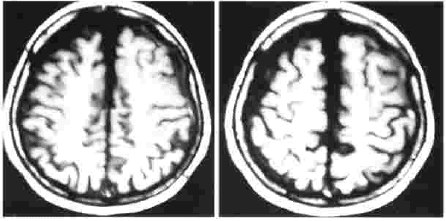

Las imágenes de resonancia magnética muestran un hematoma subdural crónico izquierdo (imagen No. 7). El paciente refiere dormir siempre sobre el lado derecho.

Los controles neurológicos periódicos no muestran signos clínicos de deterioro neurológico, desaparecen totalmente las crisis de paresias en el miembro superior derecho. Las imágenes de resonancia magnética realizada al mes, muestra

Imagen No. 7. Resonancia magnética cerebral inicial.

Imagen No. 8. Resonancia magnética cerebral a las 4 semanas.